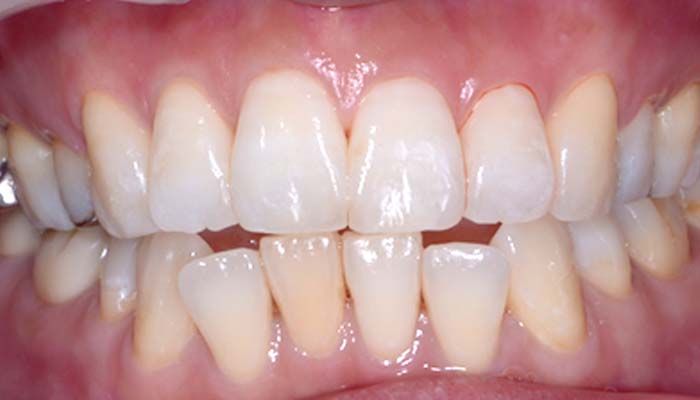

症例2. 下顎のみ部分矯正

治療前

治療後

治療期間 | 6ヶ月 |

治療費 | 20万+tax (別途調整料) |